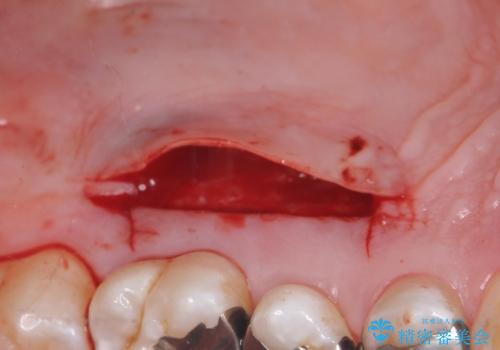

退縮した歯茎に対して移植をすることで、しみる場所を覆う計画です。

歯根の分岐部よりも根尖側の頬側面が露出している状態でしたが、露出部位を分岐部までに抑えることができました。